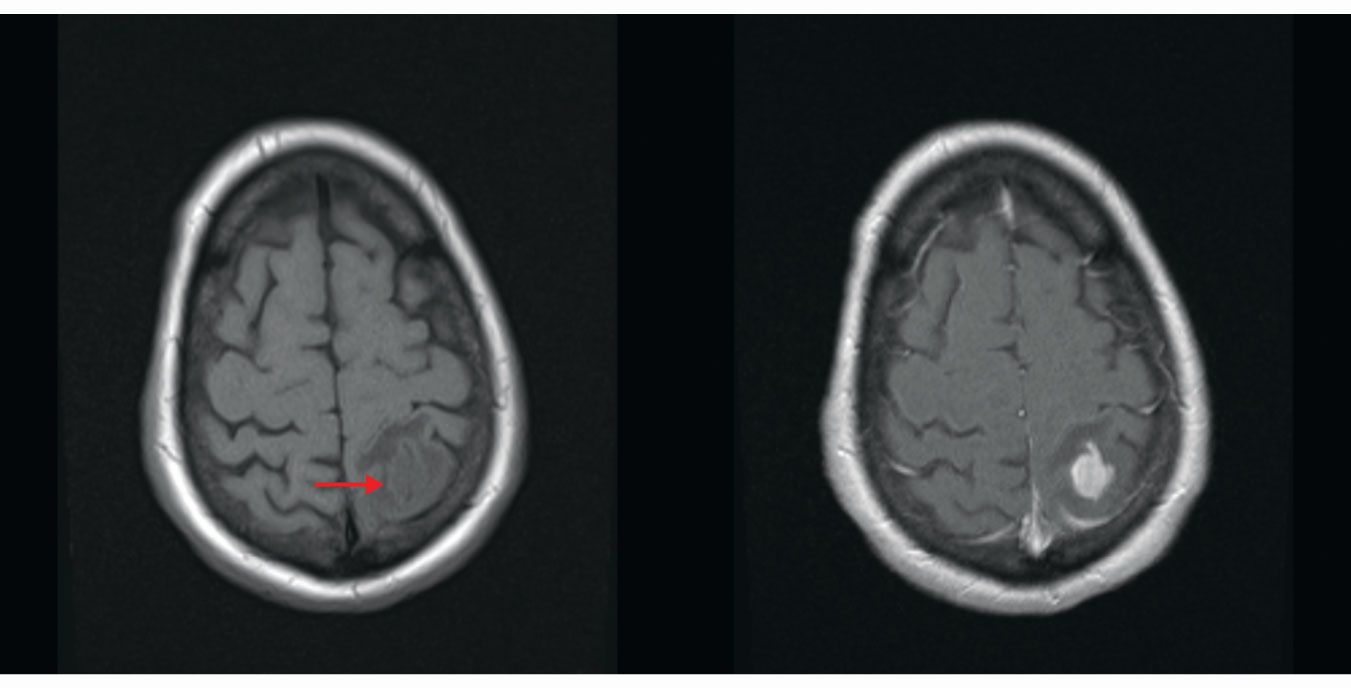

Figure 3.

T1-weighted images of a brain without (left) and with (right) gadolinium contrast dye. The tumor (red arrow) is only subtly visible without the contrast; new blood vessel formation in the tumor results in high uptake of the dye, which makes the tumor much more visible in the contrast-enhanced image. (Images by David Jordan, University Hospitals Cleveland Medical Center.)